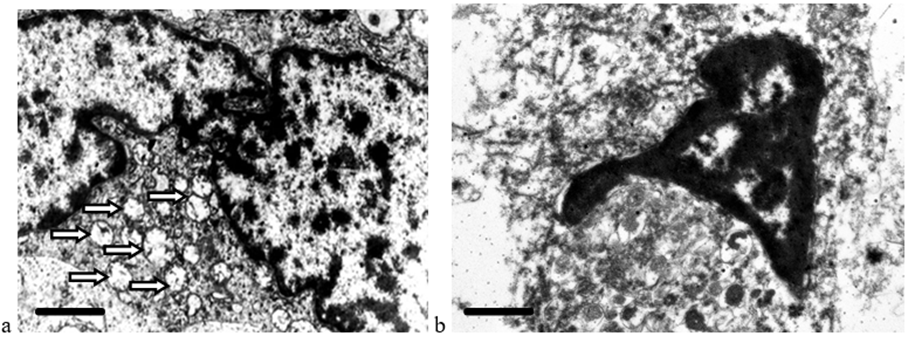

Comparison of ultrastructural changes in HCC (Figure 3) and CRCM (Figure 4) cells after cryotherapy revealed similar changes, manifested in a complex of morphological alterations in the nucleus (deformation, wrinkling, compaction, and uneven, coarse chromatin condensation), characteristic of karyopyknosis and karyorrhexis—irreversible destructive processes. In HCC cells, the karyolemma was not visualized almost throughout its entire length, the nucleoplasm had a fine-granular appearance. Pronounced edema and homogenization of the cytoplasm, destruction of mitochondria and other organelles, did not allow differentiating mitochondria, which became an objective obstacle to conducting morphometric analysis (Figure 3). In CCC cells, pronounced destructive changes were noted, however, the ability to differentiate mitochondria after cryodestruction allowed for a comparative morphometric analysis of these organelles before and after cryotherapy (Figure 5). The average mitochondrial area in cells after cryodestruction was 0.48 ± 0.01 μm2 compared to the data before cryodestruction - 0.15 ± 0.02 μm2, i.e. it increased 3-fold (p < 0.05) (Table 2).

Figure 3: Destructive changes in HCC cells: a – tumor cell ultrastructure before cryodestruction, mitochondria – white arrow; b – devitalization of the malignant cell after cryodestruction; destruction of all intracellular organelles; homogenization of the nucleu (N); absence of nucleolemma, plasmalemma. The length of the scale line corresponds to 1 μm.

Figure 4: Destructive changes in CRCM cells: a – tumor cell ultrastructure before cryodestruction, mitochondria – white arrow; b – absence of plasma membrane, nucleolemma, destruction of intracellular organelles after cryotherapy. The scale line length corresponds to 1 μm.